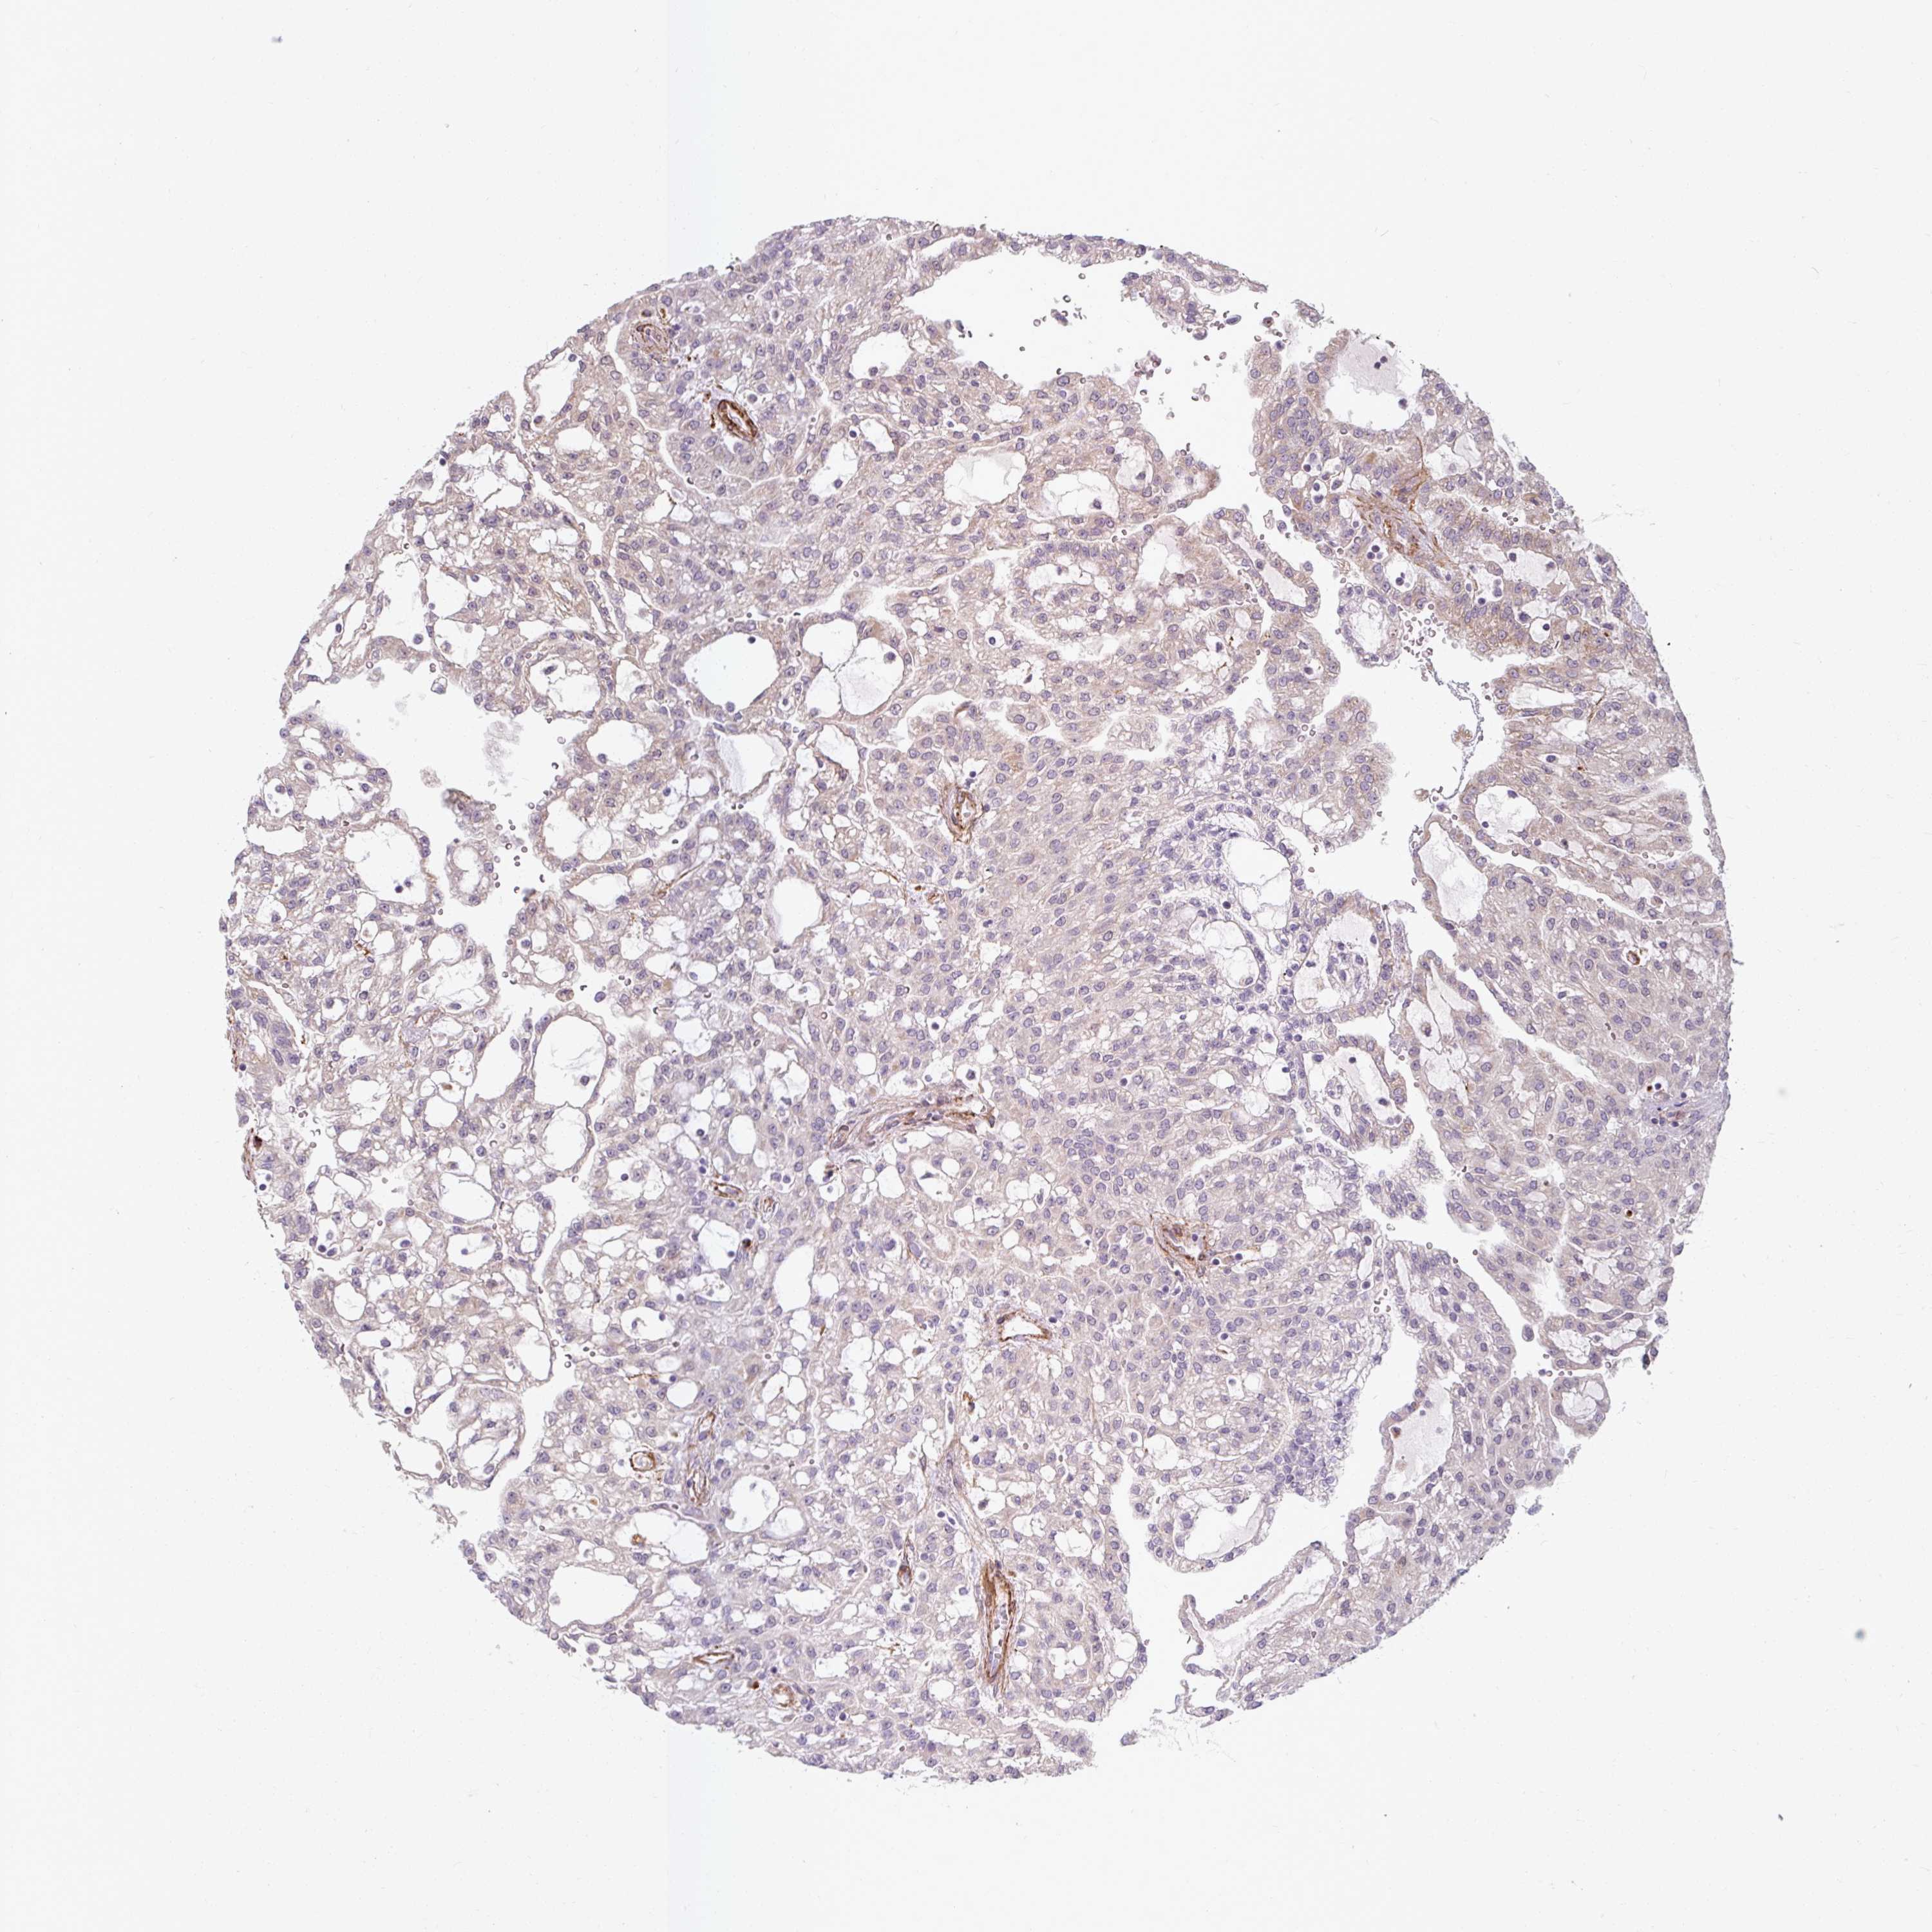

KIDNEY RENAL PAPILLARY CELL CARCINOMA (TCGA) - Interactive survival scatter ploti

The Survival Scatter plot shows the clinical status (i.e. dead or alive) for all individuals in the patient cohort, based on the same data that underlies the corresponding Kaplan-Meier plots. Patients that are alive at last time for follow-up are shown in blue and patients who have died during the study are shown in red.

The x-axis shows the expression levels (FPKM) of the investigated gene in the tumor tissue at the time of diagnosis. The y-axis shows the follow-up time after diagnosis (years). Both axes are complimented with kernel density curves demonstrating the data density over the axes. The top density plot shows the expression levels (FPKM) distribution among dead (red) and alive patients (blue). The right density plot shows the data density of the survived years of dead patients with high and low expression levels respectively, stratified using the cutoff indicated by the vertical dashed line through the Survival Scatter plot. This cutoff is automatically defined based on the FPKM cutoff that minimizes the p-score. The cutoff can be changed by dragging the vertical line or by entering a cutoff value in the square labeled "Current cut-off".

Under the Survival Scatter plot the p-score landscape (black curve; left axis) is shown together with dead median separation (red curve; right axis). Dead median separation is the difference in median mRNA expression between patients who have died with high and low expression, respectively. It is calculated as follows: median FPKM expression of dead patients with high expression - median FPKM expression of dead patients with low expression. This is intended to aid the user in visually exploring custom cutoffs and the associated p-scores and dead median separation.

Individual patient data is displayed and can be filtered by clicking on one or more of the category buttons on the top of the page. Categories describing expression level and patient information include: high, low, alive, dead, female, male and tumor stages. The scale of the x-axis can be toggled between linear and log-scale by clicking on the "x log" button. Mouse-over function shows TCGA ID, patient information and mRNA expression (FPKM) for each patient.

& Survival analysisi

Kaplan-Meier plots summarize results from analysis of correlation between mRNA expression level and patient survival. Patients were divided based on level of expression into one of the two groups "low" (under cut off) or "high" (over cut off). X-axis shows time for survival (years) and y-axis shows the probability of survival, where 1.0 corresponds to 100 percent.

MRPS5 is not prognostic in Kidney Renal Papillary Cell Carcinoma (TCGA)

Best expression cut offi

Based on the FPKM value of each gene, patients were classified into two groups and association between prognosis (survival) and gene expression (FPKM) was examined. The best expression cut-off refers the FPKM value that yields maximal difference with regard to survival between the two groups at the lowest log-rank P-value. Best expression cut-off was selected based on survival analysis .

When clicking on this number, the vertical dashed line indicating cut-off, the interactive survival plot, and the Kaplan-Meier curve will be adjusted to show results based on the best expression cut-off.

: 6.64